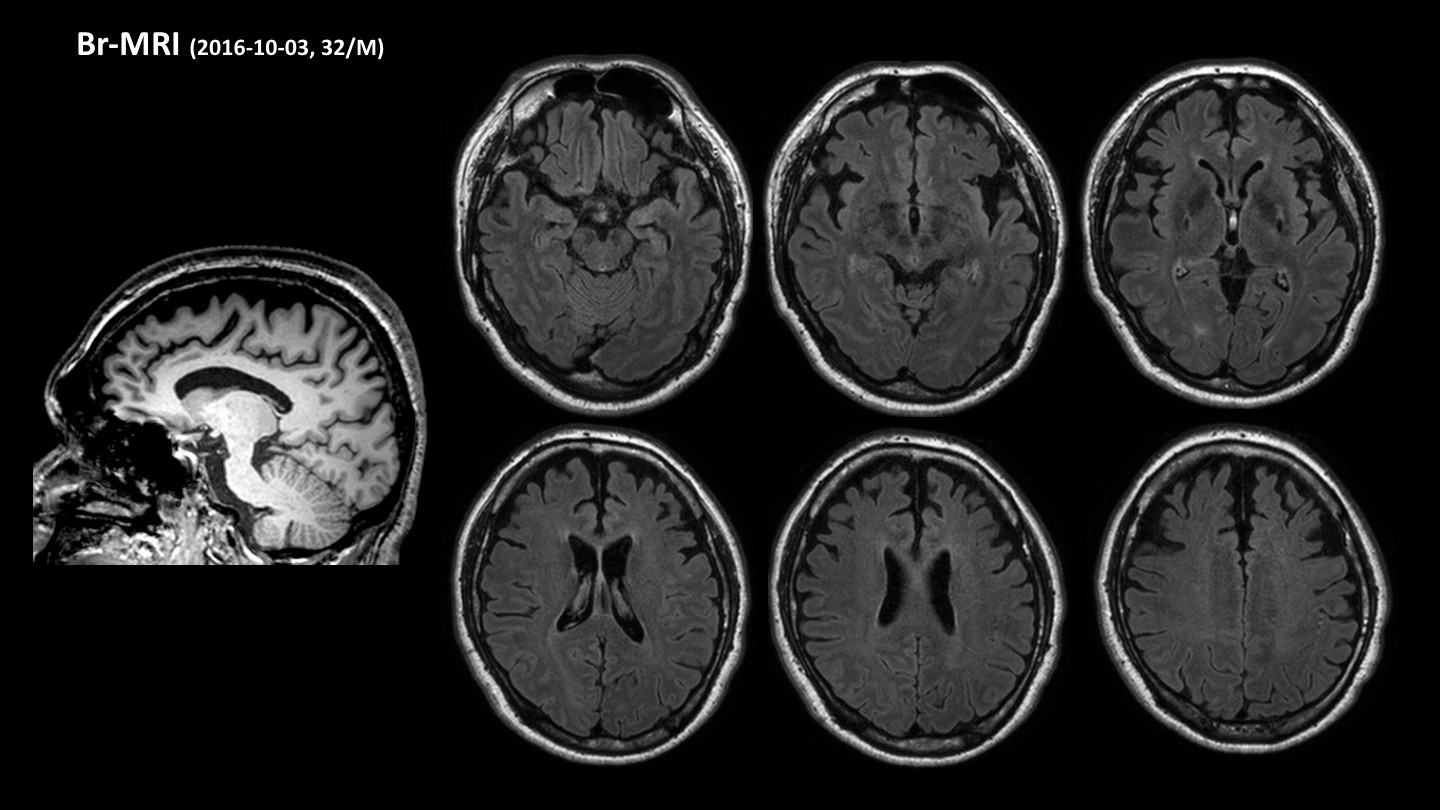

현재 삼성서울병원 신경과 교수로 재직 중이신 김준표 교수님은 신경과 레지던트, 전임의, 임상조교수로 활동하시며 대한치매학회 위원으로서 치매와 신경과학 분야에서 깊은 전문성과 풍부한 경력을 쌓아오셨습니다. 특히, SCI급 논문 55편을 게재하며 학문적 연구에도 크게 기여하셨습니다. 이번 강연에서는 치매의 진단, 치료, 예방에 대한 귀중한 통찰을 나눠주실 예정입니다.

현대사회에서 치매는 우리 주변에서 점점 더 빈번하게 접할 수 있는 중요한 건강 문제로 떠오르고 있습니다. 이번 강의를 통해 치매를 진단하고, 효과적으로 치료하며, 예방할 수 있는 실질적인 방안에 대해 알아볼 수 있는 소중한 시간을 가질 수 있을 것 같습니다. 치매 분야에서 오랜 경험을 지닌 교수님의 강의를 통해 치매에 대한 더 깊은 이해와 대비책을 마련할 기회를 함께 가져보시길 바랍니다.